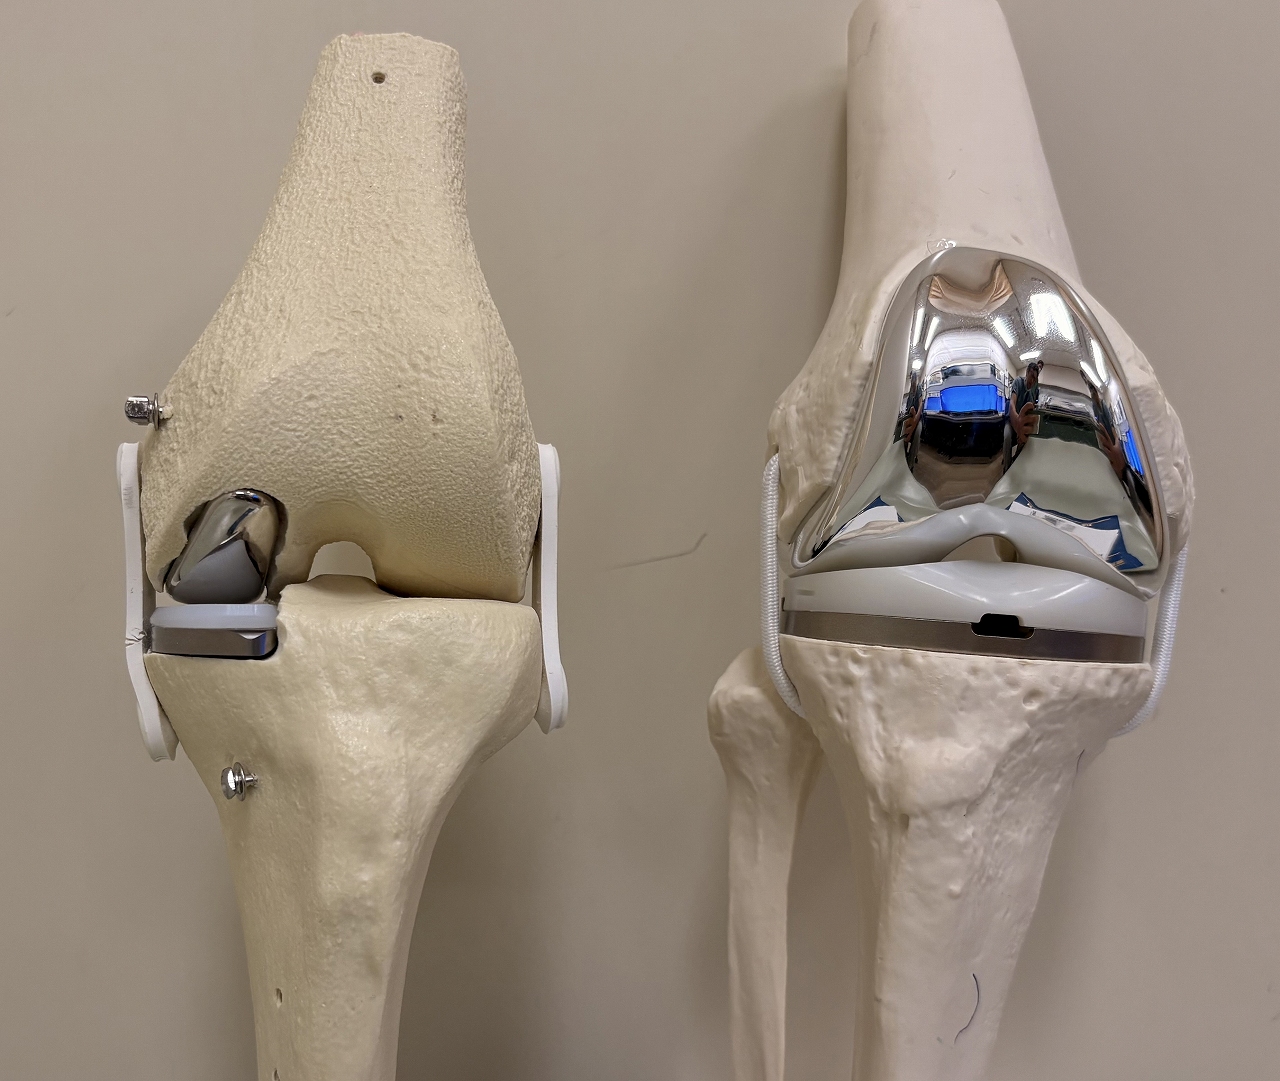

①UKA(単顆置換術)②TKA(全置換術)

人工膝関節置換術は、変形性膝関節症や関節リウマチなどによって傷んだ膝関節の表面を、人工の関節部品(インプラント)に置き換える手術です。痛みの軽減や歩行能力の改善を目的として行われます。

手術では、大腿骨や脛骨(必要に応じて膝蓋骨)の骨の表面を整え、金属やポリエチレンなどでできた人工関節を設置し、骨セメントなどを用いて固定します。これにより、関節の動きをなめらかにし、日常生活動作の改善を目指します。

また、当院で近年、症例数が増加しているUKA(単顆置換術)は、TKA(全置換術)と比較して、置換が必要な部分のみに手術範囲を限定できるという特徴があります。そのため、相対的に骨の温存性が高く、前十字靱帯をはじめとする靭帯や健常な関節面を残すことが可能です。これにより手術侵襲が抑えられ、術後の違和感が少なく、早期の機能回復が得られやすいとされています。

実際に、無作為比較試験や国内外の臨床報告において、UKA(単顆置換術)はTKA(全置換術)と比較して、術後6週間から3か月にかけて、歩行能力などの日常生活動作に関連する回復が早く、術後疼痛の軽減や入院期間の短縮が期待できる手術法であることが示されています。

一方で、UKAは一般的にTKAと比べて手術視野が限られ、健常な骨や靭帯を温存しながら関節のバランスを精密に調整する必要があるため、より高い手術精度が求められる術式でもあります。

当院ではこうした特性を踏まえ、Makoロボット支援手術システムを導入し、術前の3D計画に基づいた骨切除およびインプラント設置の精度と再現性の向上に取り組んでいます。これにより、患者さん一人ひとりの膝の形態に即した、より正確で再現性の高いUKA手術を行うことが可能となっています。

左:UKA(単顆置換)右:TKA(全置換術)